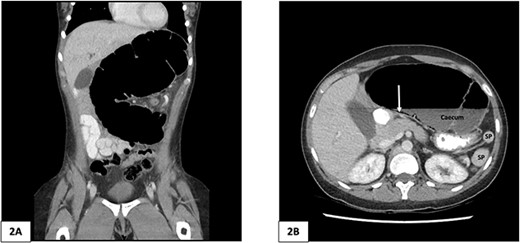

A plain abdominal X-ray was performed showing a grossly distended loop of colon in the left upper abdomen. Subsequent computed tomography (CT) scan of the abdomen and pelvis was obtained using oral and intravenous contrast with images acquired during portal venous phase. The CT showed a mesenteric whirl sign (Fig. 1A) and caecal volvulus with the caecum measuring 97 mm diameter at its most distended point with associated pneumatosis coli (Fig. 2A and B).

Computed tomography of the abdomen and pelvis of 25-year-old female patient. (A) Coronal slice demonstrating caecal volvulus with distended loop of colon. (B) Axial slice demonstrating 97 mm diameter distended caecum, multiple splenic fragments, arrow indicates pneumatosis coli, indicating colonic ischaemia. SP, spleen fragments.

There was malrotation of the gut with all colon on the left side and most of the small bowel on the right side of the abdomen (Fig. 2A). There was duplication of the infrarenal IVC, interruption of the suprarenal IVC with azygos continuation (Fig. 1C–F). A left-sided IVC draining venous blood from the left common iliac vein was present which drained into the left renal vein, while the right IVC drained blood from the right common iliac vein into the right renal vein. A retroaortic communication draining blood from the right IVC into the left IVC was also noted. From the renal veins all venous return was via the azygos vein to the superior vena cava with interruption of the suprarenal IVC. A suprahepatic IVC draining blood from the middle, left, and right hepatic veins into the right atrium was present (Fig. 1B). The spleen was divided into five distinct fragments, all within the splenic fossa and each supplied by an individual branch of the splenic artery (Figs 1 and 2).